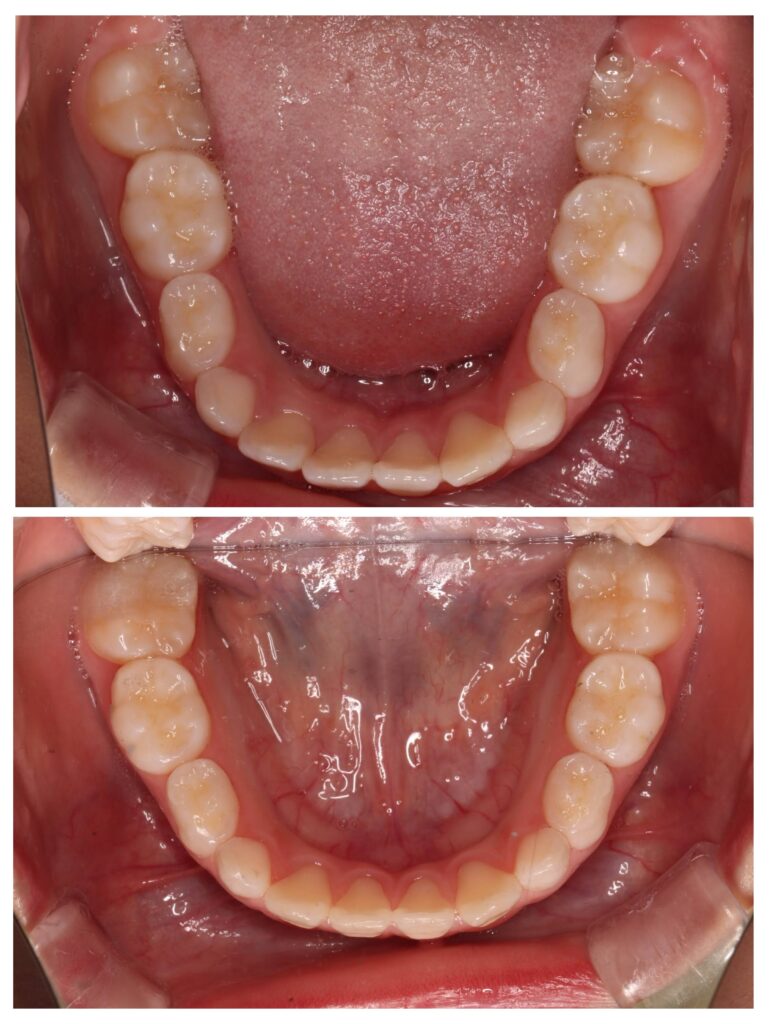

症例紹介①(顎顔面矯正)

今回の症例では、

成長期に上顎の拡大装置を使用。

BEFORE

歯列が狭く、前歯のスペース不足が認められました。

AFTER

歯列はU字型へ拡大。

永久歯が並ぶ余裕のあるアーチへ改善しました。